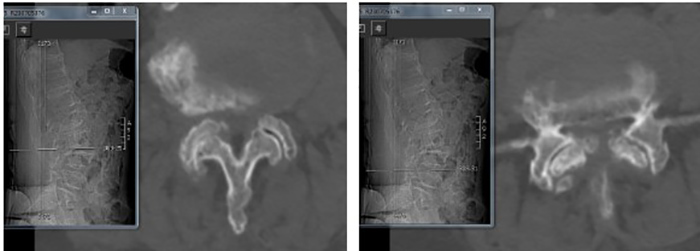

陈瑞松副主任医师接诊后,经过详细询问病史、全面查体,并结合影像学检查,诊断为腰椎椎管重度狭窄症。考虑到张阿婆年事已高,有高血压、冠心病、糖尿病、骨质疏松病史,陈瑞松副主任医师建议其采用微创手术治疗。据介绍,相较于常规开放手术,脊柱微创手术有创伤小、出血少、恢复快等优点,是高龄患者的福音。

术前影像

经过详细的术前评估和完善的术前准备,陈瑞松带领团队为张阿婆进行一个节段的单侧入路双侧减压(ULBD)手术及一个节段的双侧入路270度减压手术,仅切开了三个7毫米的小切口,一个多小时就顺利完成手术。